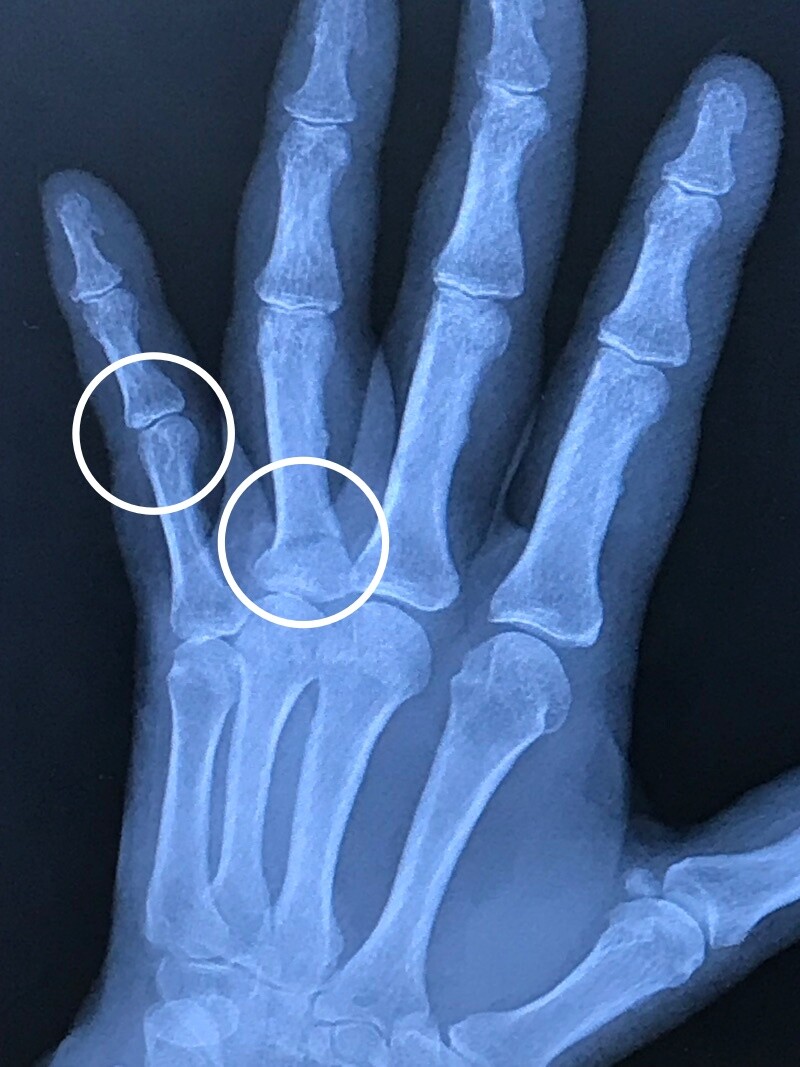

1週間ぶりに撮ったレントゲンで

新たな事実が判明。

薬指だけでなく

小指の関節の軟骨に

小さな損傷発覚。

この1週間

腫れが引かず

押さえると痛かった。